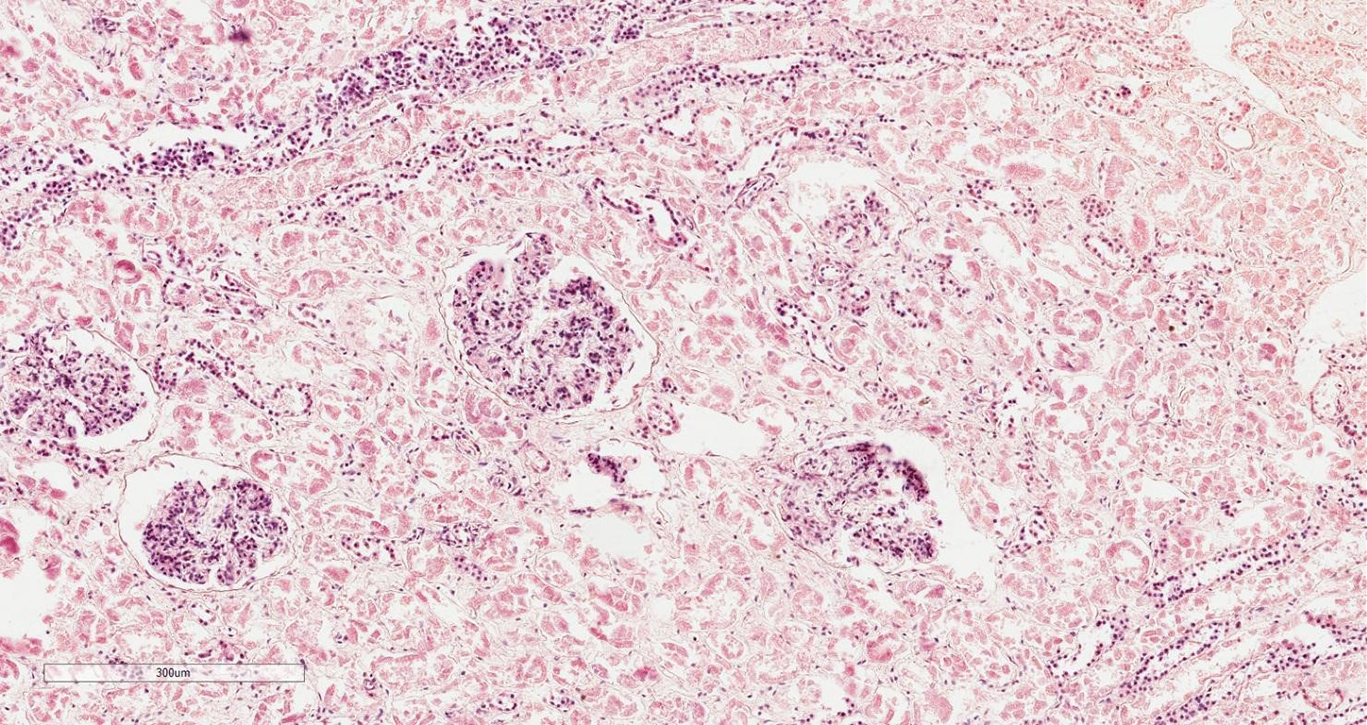

Основными морфологическими проявлениями некротического нефроза ишемического характера являются истончение или упрощение канальцевого эпителия с потерей щёточной каймы и вздутием апикальной цитоплазмы с усилением эозинофильного окрашивания. Ядра нефроцитов характеризуются конденсацией хроматина, усилением базофильного окрашивания или потерей чёткого контура ядра. Просветы канальцев заполнены отслоившимися некротическими эпителиальными клетками канальцев, остатками фибрина или гиалиновыми цилиндрами (рис. 2).

Рис. 2. Некробиотические изменения канальцевого эпителия, отёк и полнокровие интерстиция у беременной пациентки с острой почечной недостаточностью. Окраска гематоксилином и эозином; ×40.

Fig. 2. Necrobiotic changes in the tubular epithelium, edema and congestion of the interstitium in a pregnant patient with acute renal failure. Hematoxylin and eosin staining; ×40.